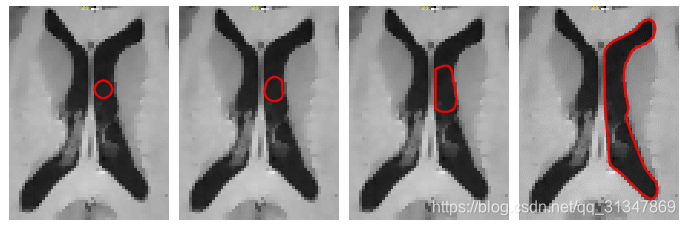

SNAP 基于名为 snake evolution 的分割方法,分割边框(蛇)会从一个粗糙的边界进化成一个比较接近组织结构的边框。

snake 的进化由一个数学表达式控制,该表达式描述了 snake 在特定时间上每个点的速度,该速度取决于1)snake 的形状;2)该点附近的图像的强度。

下面是对 snake 上速度的描述:

snake 某点的运动由该点速度矢量之和决定,虚线轮廓表示下一个时间段 snake 的形状。